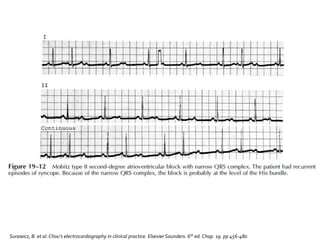

Presencia súbita de

una onda P que no

conduce a los

ventrículos

Sin prolongación

previa del intervalo PR

Nivel de bloqueo

usualmente es

infranodal.

 Al menos dos impulsos auriculares regulares

y consecutivos se conducen con el mismo

intervalo PR antes de que se presente la onda

P bloqueada

Intervalo PR

constante

Normal o

prolongado

Todas las

ondas P

conducidas

Falla súbita

de un onda

P por ser

conducida

P-P

Pausa en la

onda P no

es igual al

doble del

intervalo P-

P

Es menos común que el tipo 1 pero es más grave.

Usualmente se asocia con un patrón de bloqueo

de rama.

En presencia de un bloqueo de rama, puede

progresar a un bloqueo AV completo con síncope

Uribe Arango W. Duque Ramírez M. Medina Durango E. Electrocardiografía y arritmias. P. LA.Export Editores. Colombia. 2005.

 En la mayor parte de los casos este tipo de

bloqueo se acompaña de síntomas

 Mareo

 Presíncope

 Síncope

 Sistema HIS-Purkinje

 Casi siempre por debajo del nodo AV

 30% en Has de Hiz, resto en las ramas